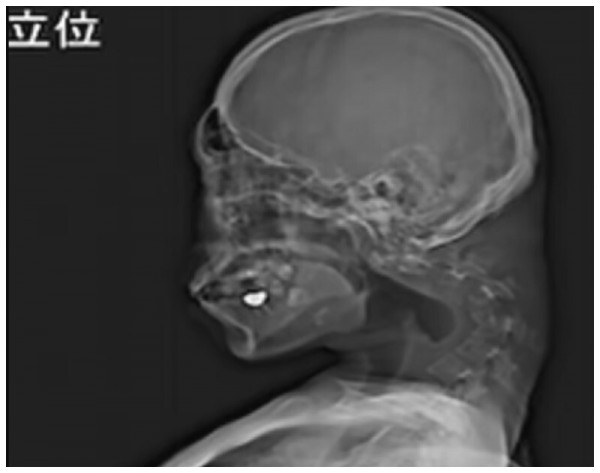

25-летний японец настолько любил играть в игры на телефоне, что практически всё свое время, не поднимая головы, прокачивал свои скилы. В результате продолжительного сидения в позе креветки у него произошла деформация шейного отдела позвоночника.

Парняга потерял возможность поднять голову, не мог нормально есть и прилично сбросил в весе. Когда ситуация уже практически достигла своего апогея, он все же решил обратиться к врачам, те знатно от увиденного удивились. Сначала медики пытались исправить синдром опущенной головы с помощью воротников - медицинских приспособлений, которые надеваются на шею и поддерживают и стабилизируют голову.

Однако, поскольку пациент жаловался на онемение при ношении устройств, данное лечение было прекращено. Решили проблему сурово, провели парочку операций, удалили лишнее, вкрутили ему в шею ряд винтов и металлических стержней, чтобы исправить осанку.